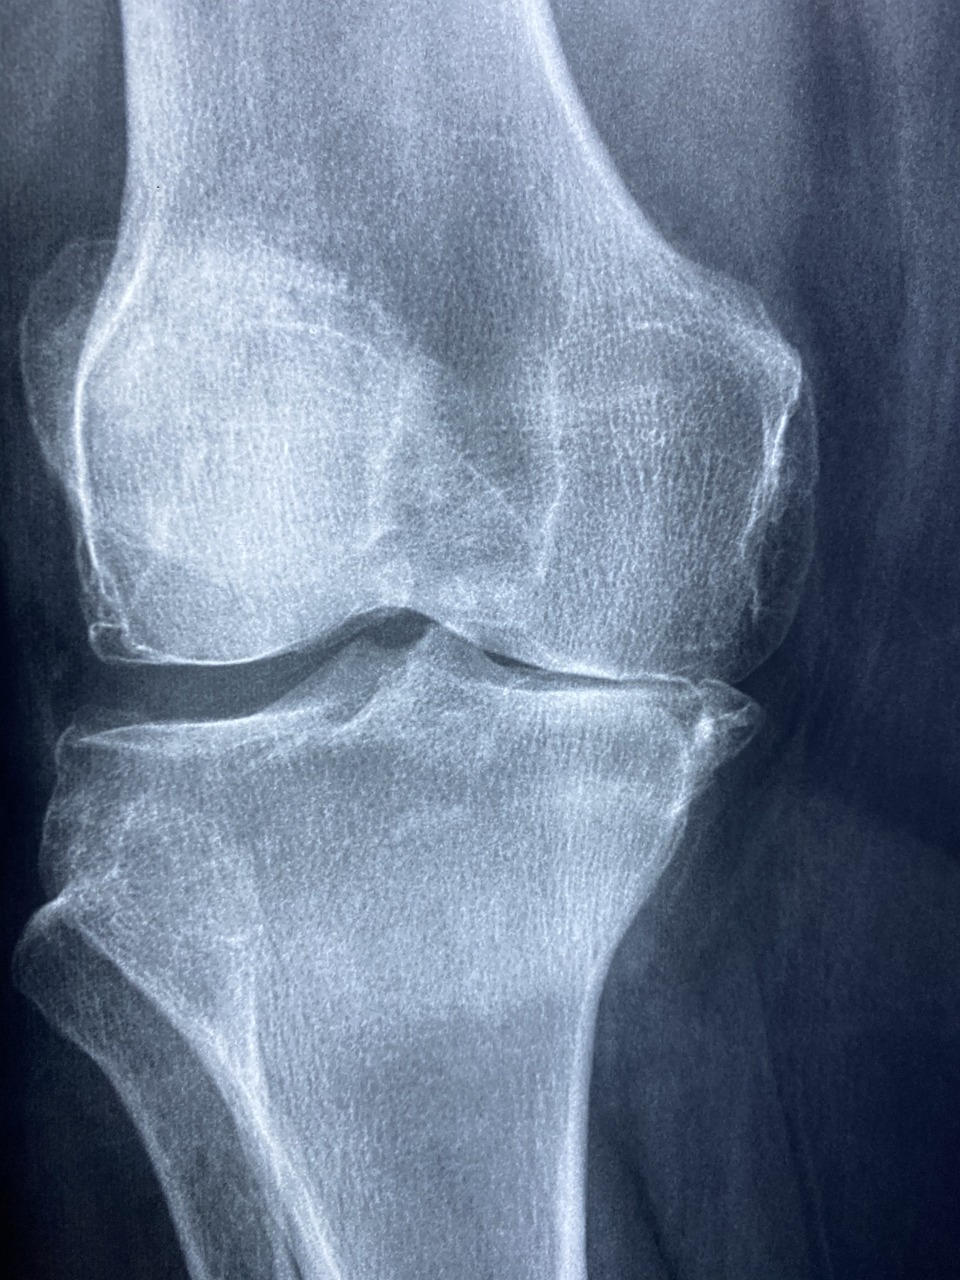

콘드로이친은 우리 몸의 연골을 구성하는 주요 성분 중 하나입니다.

특히 관절 연골에 풍부하게 존재하며, 관절의 쿠션 역할을 담당합니다.

이런 특성 때문에 콘드로이친은 관절 건강 보조제로 널리 사용되고 있죠.

- 관절 통증 완화: 콘드로이친은 관절의 염증을 줄이고 통증을 완화하는 데 도움을 줍니다.

- 연골 보호: 콘드로이친은 연골의 분해를 억제하고 재생을 촉진합니다.

- 관절 유연성 개선: 콘드로이친은 관절의 움직임을 부드럽게 만들어줍니다.

- 골관절염 증상 완화: 콘드로이친은 골관절염 환자의 증상을 개선하는 데 도움을 줄 수 있습니다.